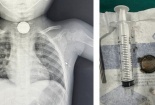

Công ty Cổ phần Dược phẩm Me Di Sun bị phạt do vi phạm trong lĩnh vực y tế

(VietQ.vn) - Thanh tra Bộ Y tế vừa ban hành quyết định xử phạt vi phạm hành chính trong lĩnh vực y tế đối với Công ty Cổ phần Dược phẩm Me Di Sun.